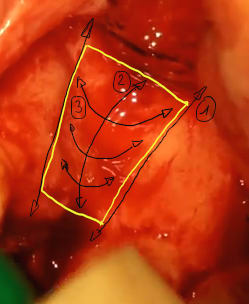

Comme le titre de ce sujet s'y prête bien et en attendant que le concept d'usinage des greffons allogéniques soit validé, je vous expose ma méthode pour adapter au mieux un greffon (allogénique ou autogène)

règles de base:

-on retouche prioritairement le greffon ailleurs que dans les zones où il doit redonner le maximum de volume

-il faut observer la forme du défaut osseux selon 3 axes: frontal, vertical et latéral et on adapte la forme du greffon pour chacune de ces vues

1°) frontalement: on regarde les berges mésiales et distales du défaut, elles peuvent être parallèles entre elles, convergentes ou divergentes, (voir vues ci-dessous)

et on taille les bords latéraux du greffon en fonction de ces berges.

2°) latéralement: il faut observer la forme générale de la concavité du défaut et on taille alors l'intrados du greffon pour épouser cette concavité générale et on prend garde de tailler le moins possible à l'endroit ou on a besoin de garder de l'épaisseur (généralement dans la partie coronaire du greffon)

3°) verticalement: on observe la forme générale de la concavité du défaut, cette concavité peut varier entre la partie coronaire du défaut et sa partie apicale. On reproduit la forme convexe correspondante à l'intrados du greffon

après ces 3 étapes le greffon est généralement déjà bien adapté.Il faut parfois cependant ajuster l'intrados dans les cas (nombreux) où il existe un gradiant de courbure des concavités de haut en bas et latéralement.

Pour des formes plus tarabiscotées, certains prennent l'empreinte de la forme du défaut avec de la cire à os pour mieux visualiser en positif les subtilitées géographiques du défaut.